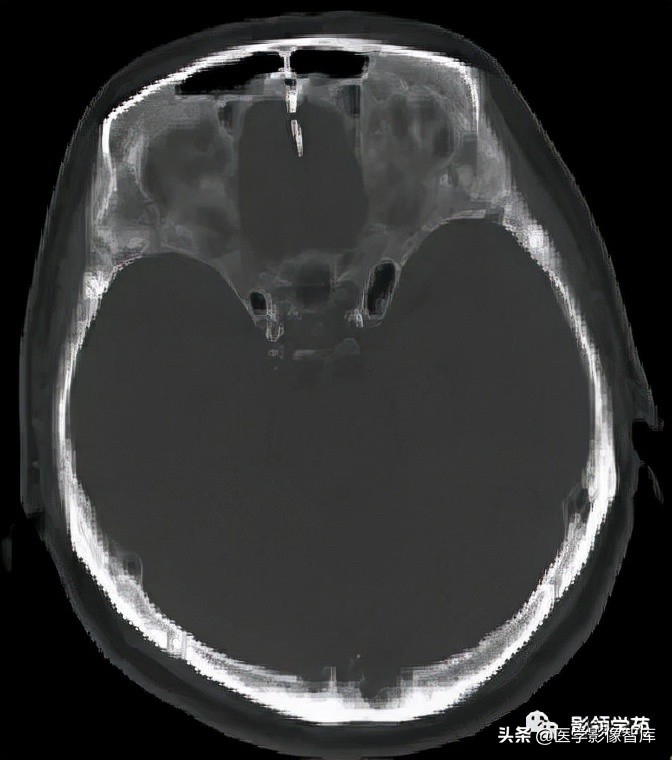

女 72岁,发现糖尿病3年余

鞍上区见一团块状稍高密度影,边界尚清,密度均匀。

鞍上右上方见一类椭圆形流空影。

病灶明显强化(瘤内血栓未强化),边界清楚,与右侧颈内动脉海绵段分界不清。垂体大小、形态未见异常。